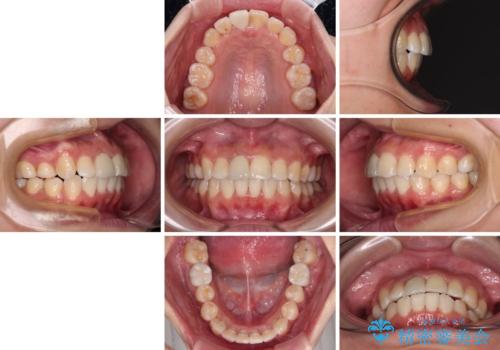

- 放置した虫歯や抜いたままの奥歯、前歯のデコボコを気にして来院された患者様です。

口元の突出感は少なく、下顎の叢生は軽微なものであったので、叢生の強い上顎左右の小臼歯を1本ずつ抜歯し、ワイヤー装置にて矯正治療を行うこととしました。

矯正治療を行う前に、根管治療の必要な上顎前歯と下顎大臼歯の根管治療を行い、矯正治療の途中で下顎の欠損部にインプラント埋入することとし、矯正治療後に補綴治療を行うこととしました。

矯正治療をしたいと思っていたが、放置している虫歯が多いため、どこに相談に行けば良いのか分からずにいたそうですが、当院の総合歯科診療を見て来院されたそうです。

矯正治療中にインプラント埋入を行うなど、余計な時間や無駄のない治療を行うことができました。